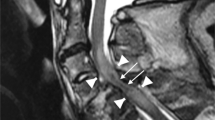

Independent variables

All preoperative MRI were performed on a 1.5 Tesla MRI scanner (Magnetom Avanto, Siemens Healthineers, Erlangen, Germany) using a standardized protocol consisting of sagittal T2 TSE, sagittal T1 TSE, sagittal STIR, sagittal 2D MEDIC, axial 2D MEDIC and axial T2 TSE sequences. The following three MRI parameters were analyzed as potential predictors of the neurological outcome: (1) presence or absence of intramedullary hemorrhage (binary), (2) lesion length (continuous), and (3) MSCC (continuous). A single observer (medical student) performed all radiological measurements with the training and supervision from a senior orthopedic resident and a spine surgeon experienced in interpreting MRI for TSCI. All measurements were reviewed by the spine surgeon. The presence of intramedullary hemorrhage was diagnosed from a hypointense signal on T2 images with a thin rim of hyperintensity [6,7,8]. Lesion length was measured in millimeters as the maximum cranio-caudal length of signal abnormality on sagittal T2 images, which includes signals from cord edema, contusion and hemorrhage [6, 7]. MSCC was calculated from mid-sagittal T2 weighted images, and refers to the percentage decrease in sagittal diameter of the spinal cord at the level of maximum spinal cord compression with respect to the expected sagittal diameter of the spinal cord (mean value of the sagittal diameter measured at the uninjured levels directly above and below the level of maximum spinal cord compression) [13]. More specifically, we used the following formula: